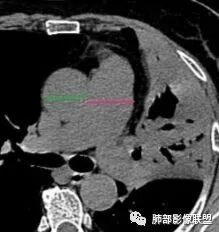

2.纵隔左移。肺动脉增宽。

1.左肺上叶较大范围实性密度区,支气管未见阻塞,无壁空洞,整体比较“干”,加之纵隔左移,比较符合病程较长的结核性病变。

2.“胸闷、气促”以及呼衰的临床表现,难以以当前肺部的病灶加以解释。

D-二聚体升高,肺动脉成像等明确患者肺栓塞的存在!